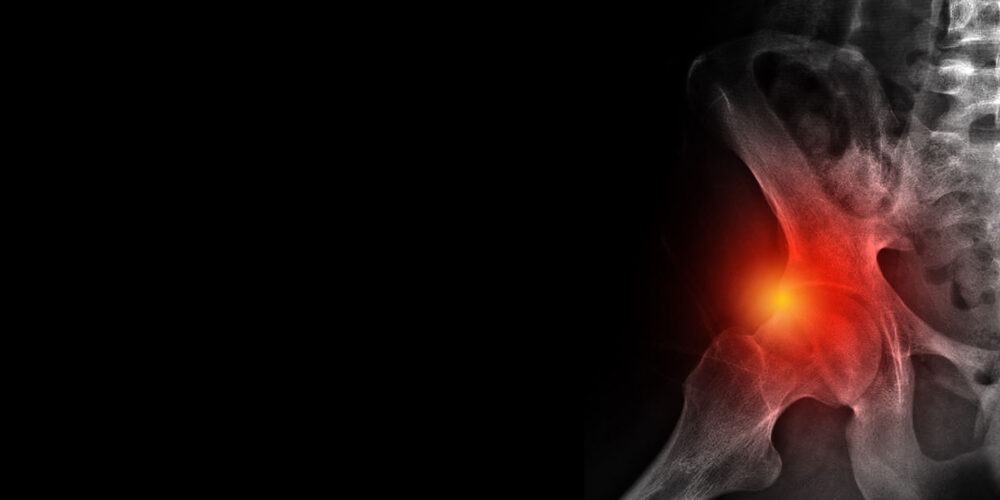

Σύνδρομο Πρόσκρουσης Ισχίου

Αφορά την παθολογική μετατόπιση και μετακίνηση της μηριαίας κεφαλής εκτός της κοτύλης όπου κινείται με αποτέλεσμα τον πόνο και την παρεμπόδιση της πλήρους κινητοποίησης της άρθρωσης. Αυτό συμβαίνει είτε λόγω πιθανής βλάβης του χόνδρου του ισχίου είτε βλάβης στον επιχείλιο χόνδρο της κοτύλης.

Αναφερόμενο χρόνιο άλγος της περιοχής του ισχίου με ταυτόχρονη ακαμψία, περιορισμό των στροφών του ισχίου ή αίσθημα χαλαρότητας της άρθρωσης.

Η κλινική εικόνα καθώς και ακτινολογικός έλεγχος, δύναται να επιβεβαιωθούν με μαγνητική τομογραφία.